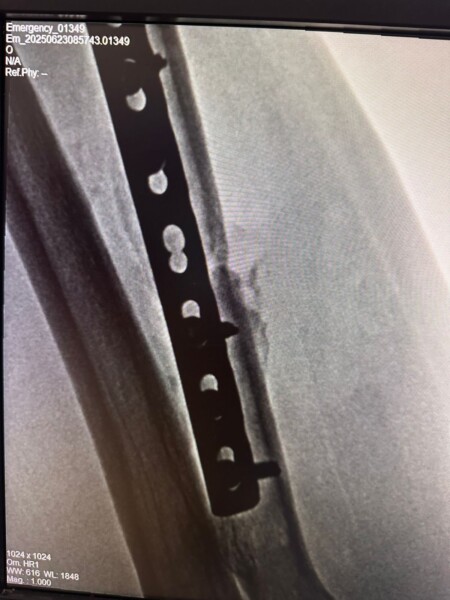

Realizamos con éxito una intervención de Alta complejidad en paciente que presentaba como lesión primaria una fractura de radio proximal, luxación de codo, lesión del fibrocartílago triangular y subluxación distal de cúbito, como consecuencia de un accidente de tránsito.

Se trató de una lesión longitudinal del antebrazo con patrón criss-cross, un cuadro complejo que representa un verdadero reto quirúrgico y requiere una técnica meticulosa para garantizar la estabilidad articular y la recuperación de la función del miembro superior.

🔹 Osteosíntesis del cúbito y del radio, logrando una alineación anatómica adecuada y una fijación estable.

🔹 Estabilización radio-cubital interósea, técnica elegida específicamente por el tipo de lesión: subluxación cubital con inestabilidad de pronosupinación.